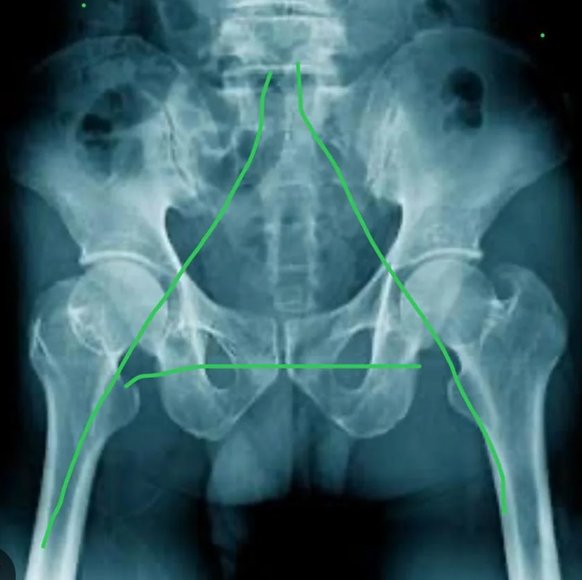

• X-rays – to assess joint space narrowing, bone changes, or osteophytes

Understanding the extent and pattern of joint damage and well as identifying whether you have osteoarthritis or inflammatory arthritis will help guide the most appropriate treatment plan.